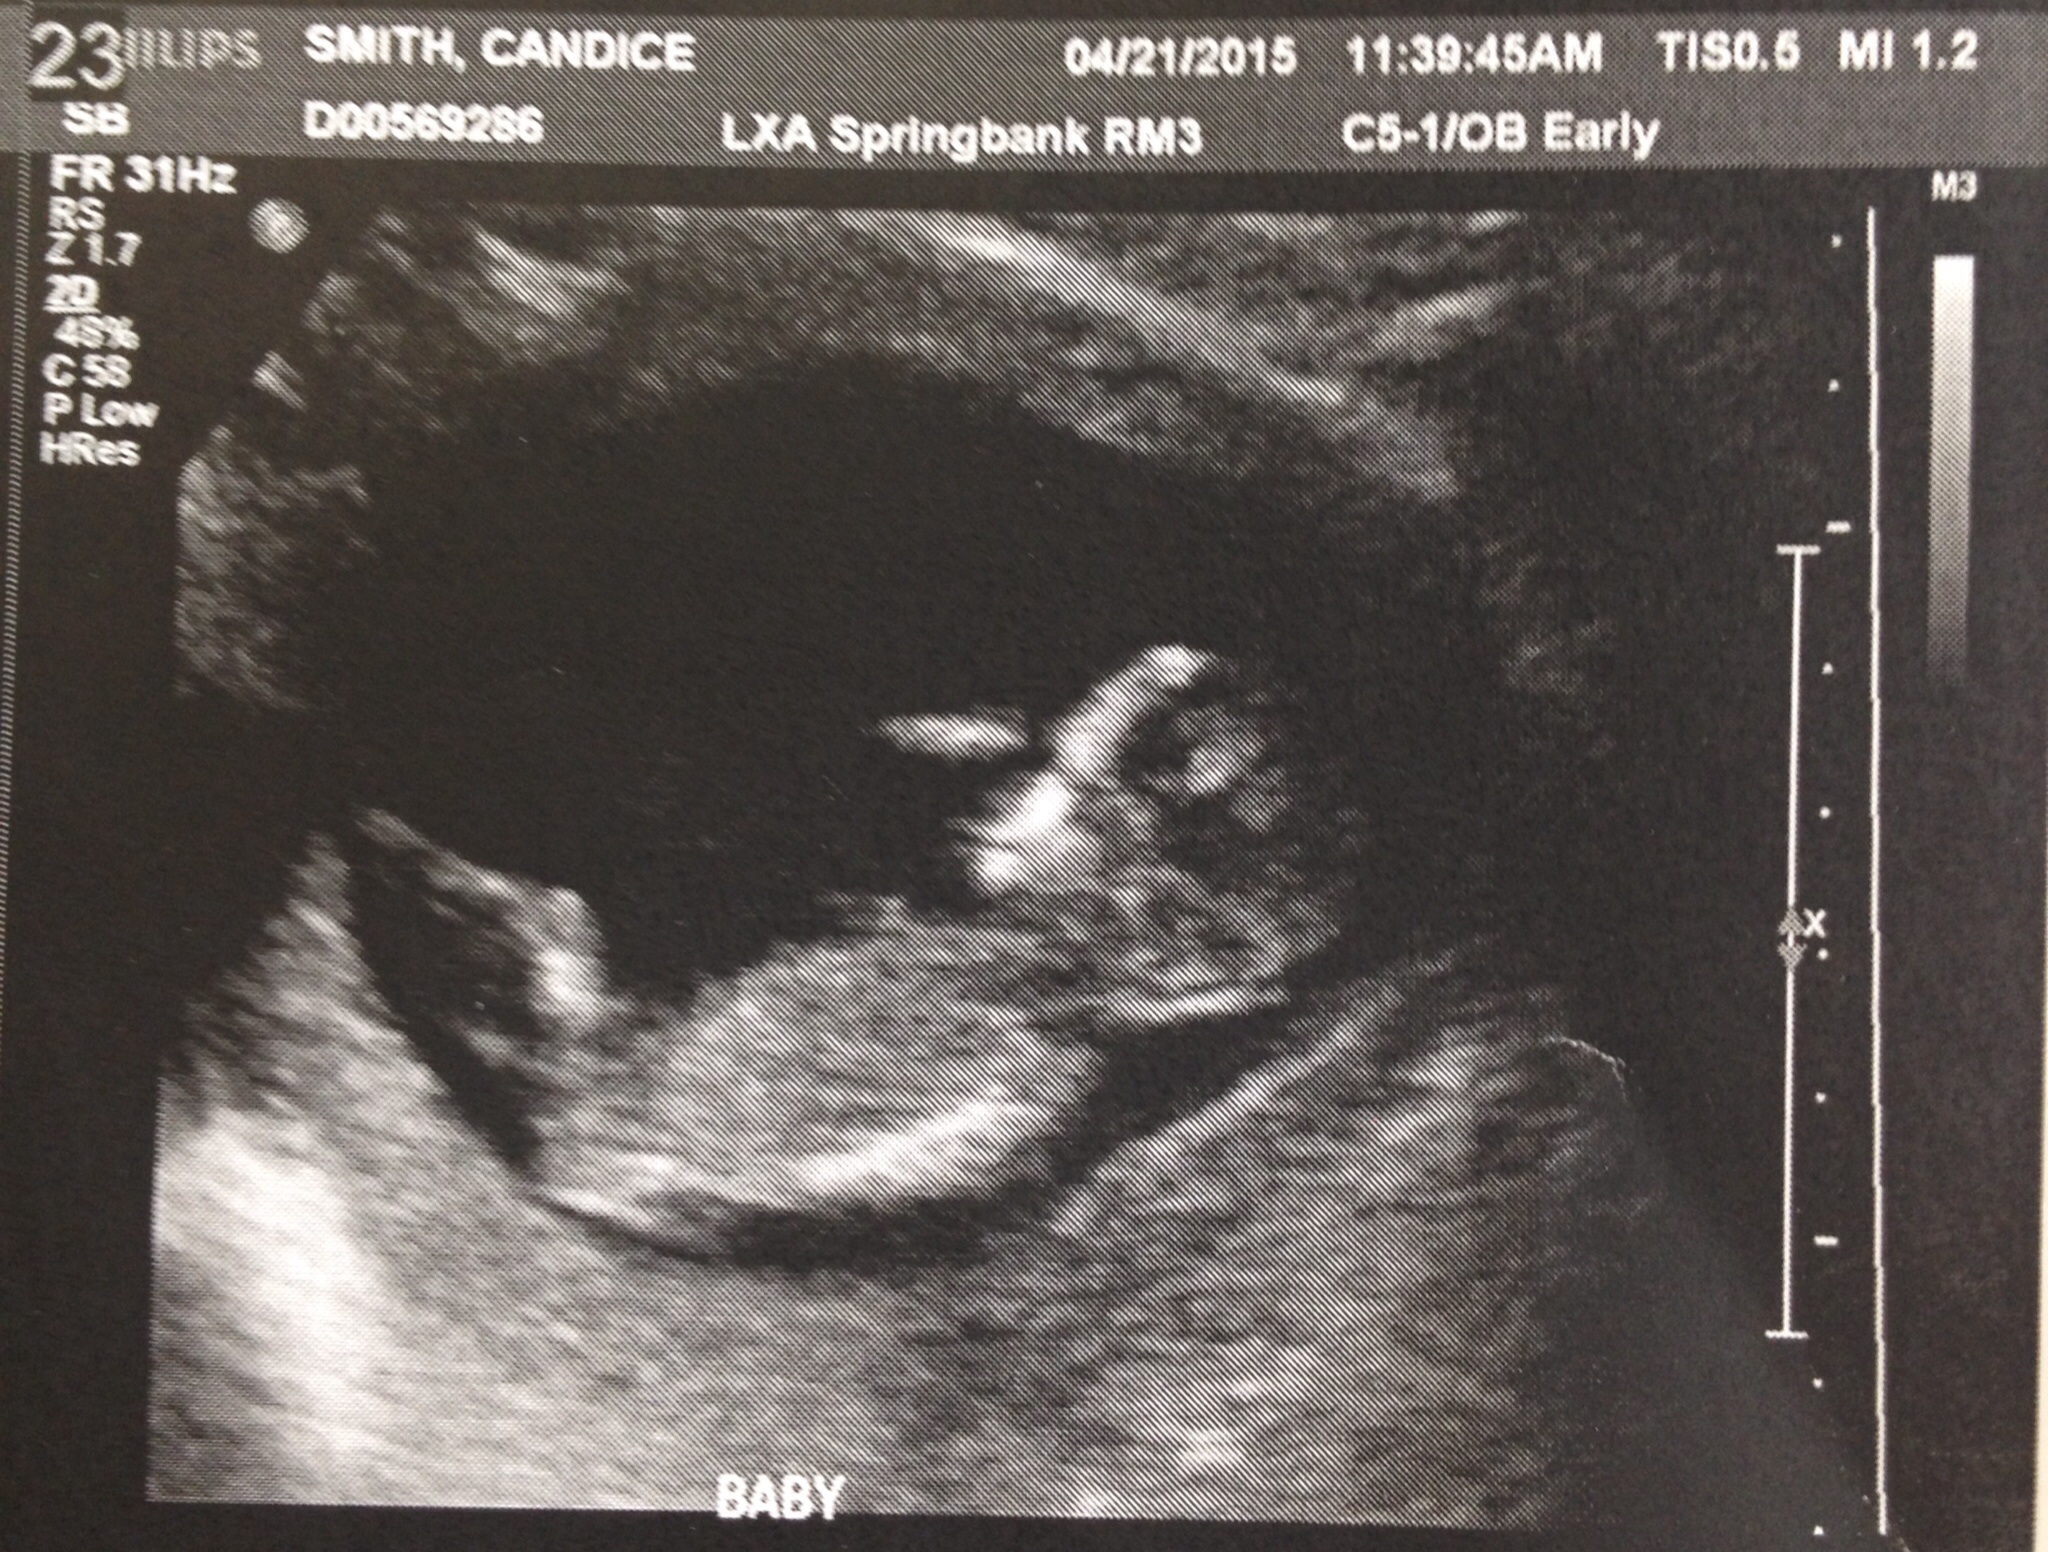

• Had my 12W ultrasound today!!!! Saw the little munchkin - heartbeat and all. 160bpm. . . Saw the measurements written on a paper but don't get actual results for two business days!

• Wow everyone's ultrasounds look so much different from 4 weeks ago.. Looks like an actual baby now! I'll be 12 weeks on Saturday and second appt on Weds so exciting! Can't believe I will be 3 months! Still a little nauseous but I THINK my energy is picking up haven't taken a nap since Sunday I think lol starting to get more of an appetite some days.. Can't wait to announce on social media!